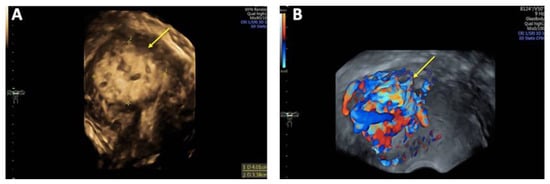

On vaginal examination, no abnormalities or active bleeding were observed. Transvaginal ultrasound revealed a retroflexed uterus measuring 81 × 51 mm, with a suspicious, irregular, hypoechoic, hypervascular lesion measuring 40 × 34 mm on the posterolateral wall of the uterus. This lesion appeared as a prominent vascular tangle extending toward the uterine cavity. Color Doppler sonography demonstrated high-velocity blood flow within the lesion, with a peak systolic velocity (PSV) of 0.3 m/s and a low-resistance pattern, indicated by a resistance index (RI) of 0.43. Distinct arterial and venous blood flow patterns were clearly visualized within the suspicious area (Figure 1 and Figure 2). Both ovaries exhibited normal physiological morphology, appearance, size, and follicle count without abnormalities.

A contrast-enhanced MRI angiography scan was performed to further confirm the diagnosis. Following administration of 6 mL Gadovist®, MRI revealed a 45 × 32 mm AVM involving both the myometrium and endometrium of the left ventrolateral uterine wall, extending to the fundus. The AVM was supplied by feeding arteries from both uterine arteries, with a predominant contribution from the left uterine artery. Venous drainage was observed via the left uterine vein, further supporting the diagnosis (Figure 3).

Figure 2. Three-dimensional transvaginal sonography (3D TVS) Imaging of uterine arteriovenous malformation (AVM): (A) 3D TVS revealing a 40 × 34 mm inhomogeneous mass (arrow) within the myometrium and uterine cavity; (B) 3D TVS color Doppler demonstrating a hypervascular lesion with turbulent blood flow characteristic of a uterine AVM (arrow).